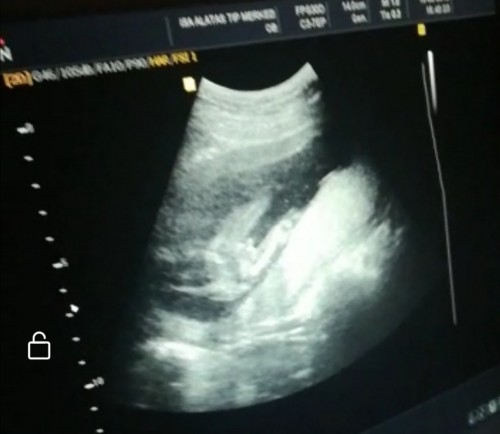

Merhaba arkadaşlar 13 haftalık gebeyim doktor bebeğe erkek dedi daha öncede başka doktor kıza benziyor demişti fotodaki ok ile gösterdiği pipisi olabilir mi yoksa göbek kordonu mu

Pipi canim o benim oglumunda oyleydi bacagi acik bi sekilde oturuyodu direk gorduk bizde

Canım bana da başta kıza benziyor dedi doktorum o zaman 14haftaydık.17haftalıkken tekrar gittik erkek bu buda pipisi dedi bacak arasındaki pipidr ama bazen kordona karıstırıyo olabilirlermş

Evet canım büyük ihtimal o pipi benim de oğlumun görmüştük geçen hafta böyleydi ve ben de 13 haftalık öğrendim erkekler erken gösterir derler :D

bak bana boyle vermislerdi oglumun pipisini